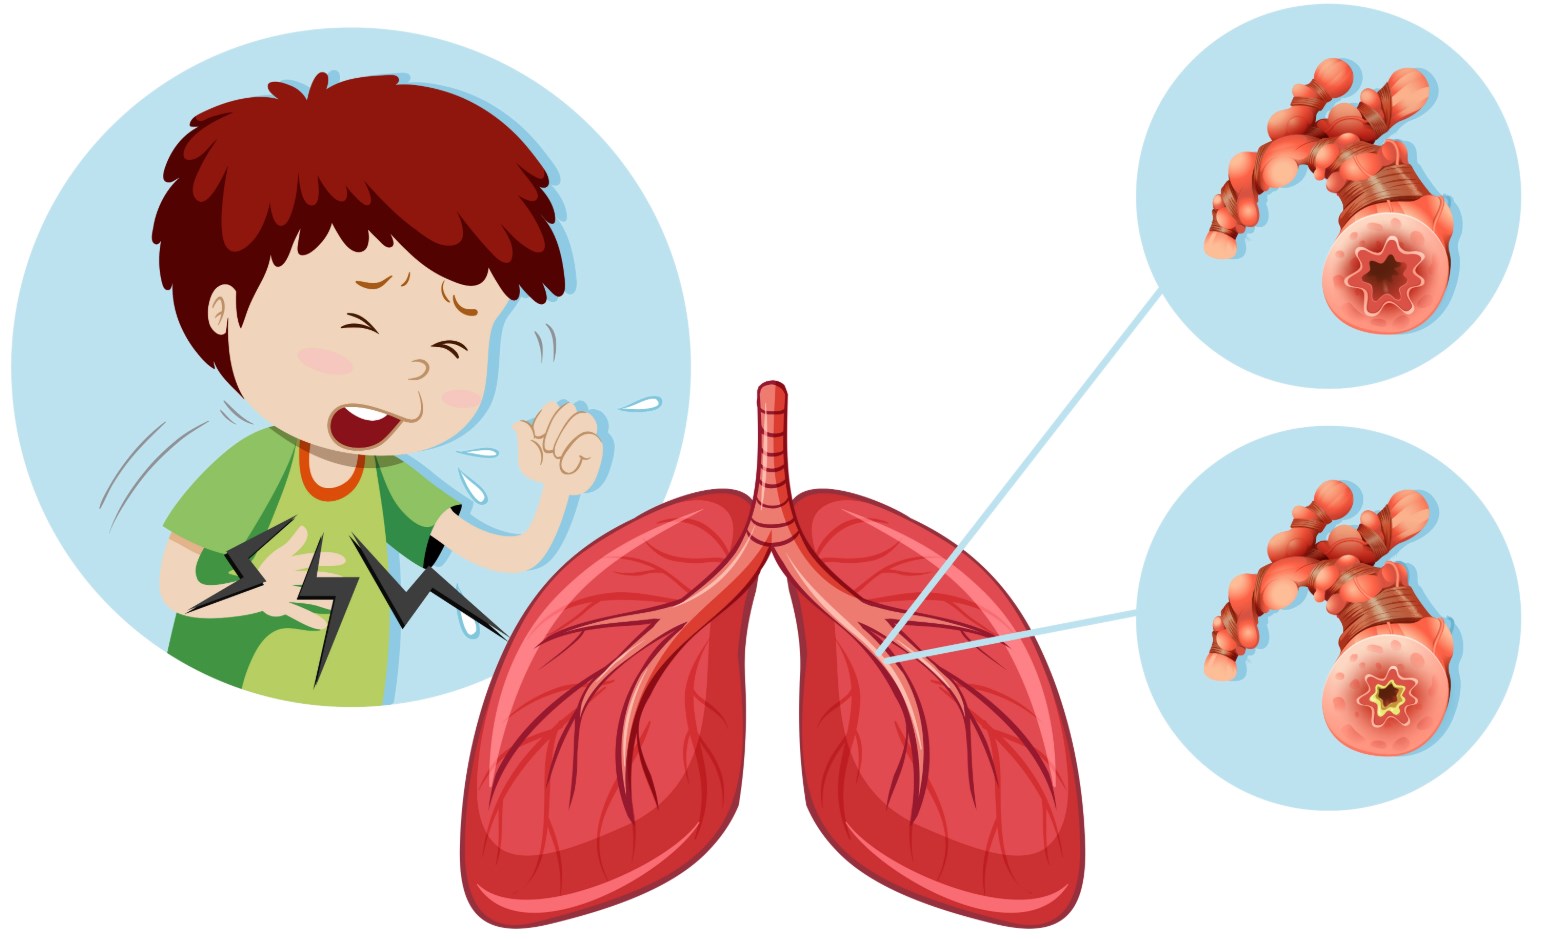

Картинки с симптомами пневмонии

В этом разделе представлены изображения, демонстрирующие различные симптомы пневмонии, такие как кашель, одышка, боль в груди и повышенная температура. Эти картинки могут быть использованы для обучения и презентаций в области медицины и здравоохранения.